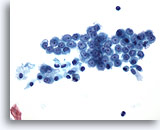

Figure 16

Pelvic wash: Benign mesothelial cells. 20X

Figure 16

Pelvic wash:

Benign mesothelial cells.

20X

A flat sheet of evenly spaced mesothelial cells in a honeycombed pattern.